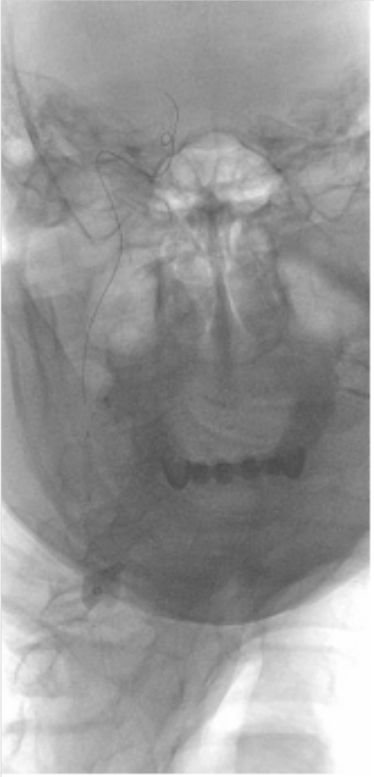

2019-06-07外院DSA:右侧颈内动脉闭塞(图2)。

图2